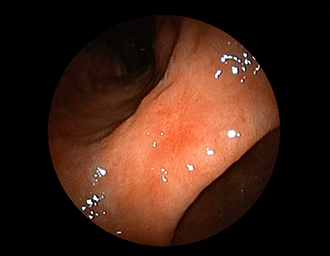

胃潰瘍(Stage S1)・・治療後5ヶ月

潰瘍の中心に白苔はなく、わずかに陥凹する潰瘍面に発赤が残る再生上皮が覆い尽くす(赤色瘢痕)。集中皺襞がなだらかに中心に延びている。→ ヘリコバクター・ピロリ感染を認めたため、除菌治療で駆除しました。

通常画像